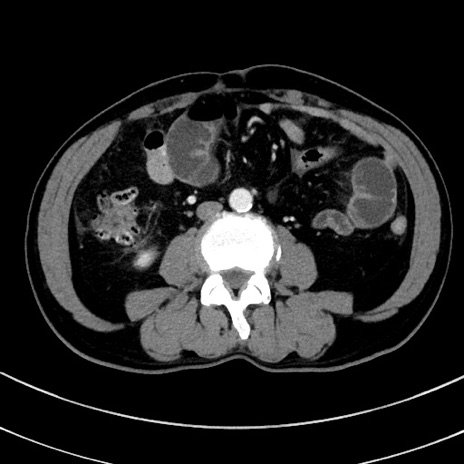

症例8(横断像)

【症例】 60歳代男性

【主訴】 黒色吐物

【現病歴】 4日前から嘔気自覚、2日前の朝食後にも嘔気あり、自分で手で嘔吐反射起こし嘔吐したところ血が混ざっていたため受診。

【既往歴】 5年前汎発性腹膜炎を伴う急性虫垂炎で手術、高血圧、前立腺肥大症、高脂血症

【身体所見】 腹部正中に手術癩痕あり 腹部平坦・軟圧痛なし膨満感あり

【データ】WBC 8400、CRP 4.54